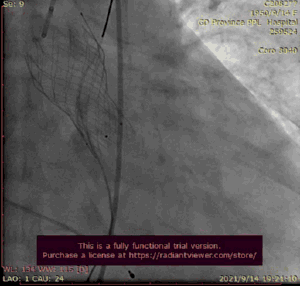

最后一枪造影

术后压差下降为10,床旁超声显示无明显瓣周漏,患者术后即刻苏醒,意识清晰,无脑部并发症。